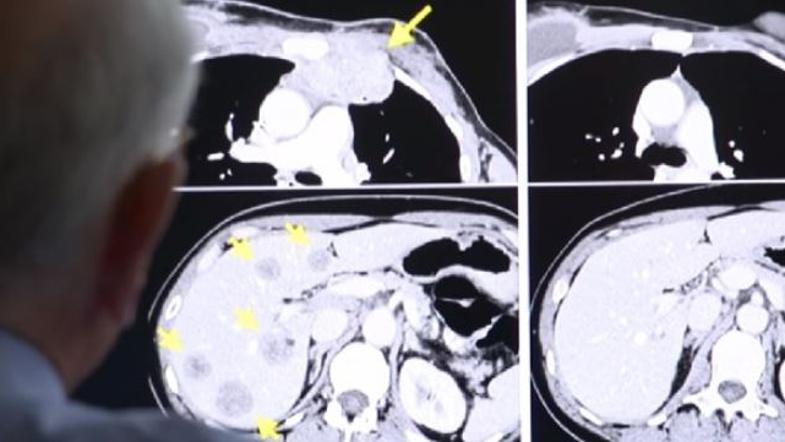

Žensko z agresivno obliko raka dojke, ki se je razširil že na druge organe, tudi na jetra, kjer je imela tumor v velikosti teniške žogice, je ekipa strokovnjakov iz ZDA ozdravila z novo ekspirimentalno terapijo. 49 letnica s Floride, ki so ji zdravniki pripisovali le še tri mesece življenja, je zdrava že dve leti.

Judy Perkins, ki živi na Floride je za BBC povedala, da je učinke terapije začela čutiti že teden dni po začetku, teden ali dva po tem pa je tumor popolnoma izginil. Kot je dejala, je bilo medicinsko osebje ob prvem slikanju "navdušeno in so vsi skakali od veselja".